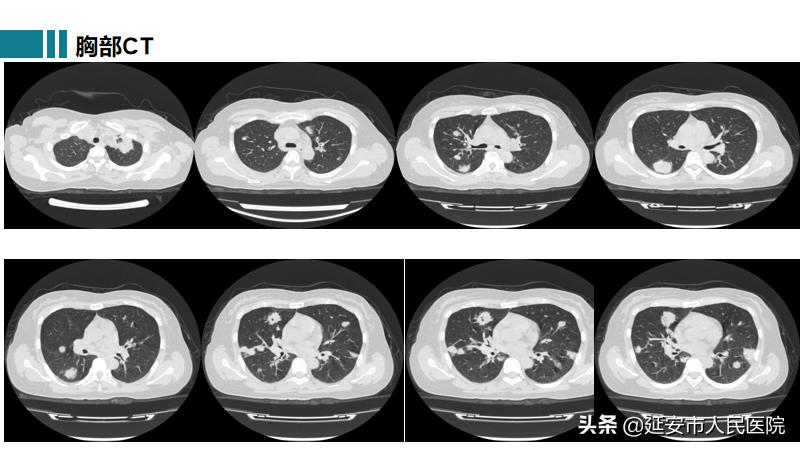

高院副主任医师接诊后,行胸部CT提示:双肺散在结节状高密度影,边界清楚,结节大小不等,部分结节内空洞形成;查体:右侧结膜充血,左侧外耳红肿、疼痛,双肺呼吸音粗,未闻及干湿啰音;化验血常规:白细胞8.7*109/L,血红蛋白96g/L,尿常规示隐血3+,D二聚体3310ng/ml,常规C反应蛋白127.54mg/L,血沉100mm/h。根据患者以上情况,首先考虑肺结核可能性最大,但患者病情进展较快,呼吸困难呈进行性加重,双下肢逐渐出现散在的出血点,不能用肺结核来解释,而且这样的胸部CT表现很少见到。面对如此复杂又难以解释的病例,高院副主任医师立即请中国医科大学驻延安医院副院长、医学博士、呼吸与危重症医学科学科带头人郑锐教授进一步诊断。

患者在最短时间被诊断为肉芽肿性多血管炎(GPA),转至风湿免疫科进行系统有效治疗后,患者精神状态好转,症状明显减轻,复查胸部CT双肺病变较前显著吸收,患者终于露出了久违的笑颜: “多亏了中国医科大学郑锐教授的一双‘火眼金睛’,帮我及时确诊了病情,让我得到有效的治疗,真的太感谢郑教授了。” 目前,患者已好转出院,后续仍在治疗中。